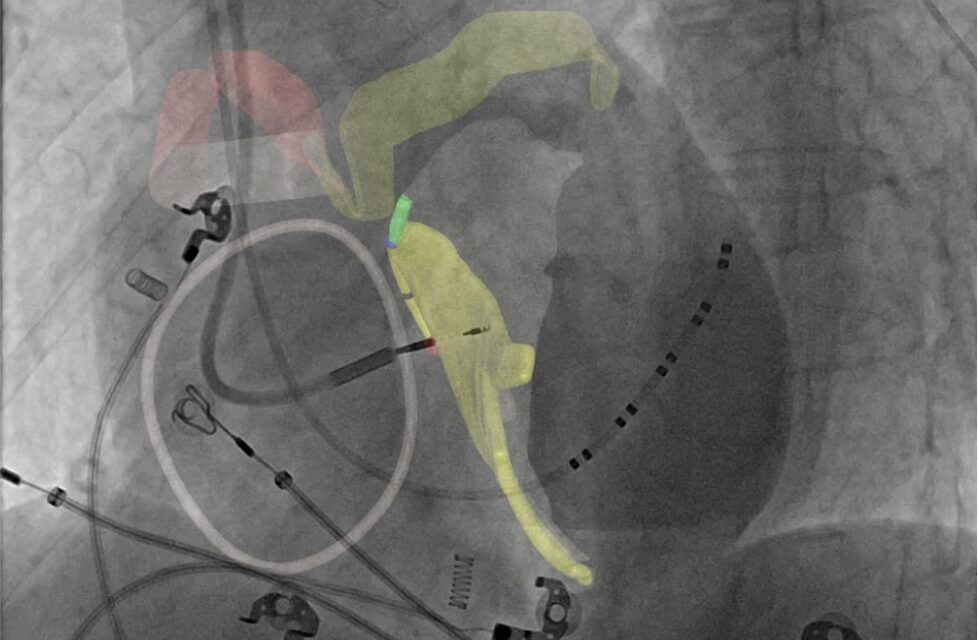

• CARA Atlas Navigator – an intraprocedural guidance platform that overlays the patient-specific conduction system model generated by Metis onto live fluoroscopic images to assist physicians during image-guided interventions.

Photo caption: CARA Atlas intra-procedural fluoroscopic overlay displaying the patient-specific cardiac conduction map generated by CARA Metis.

Photo credit: Cara Medical